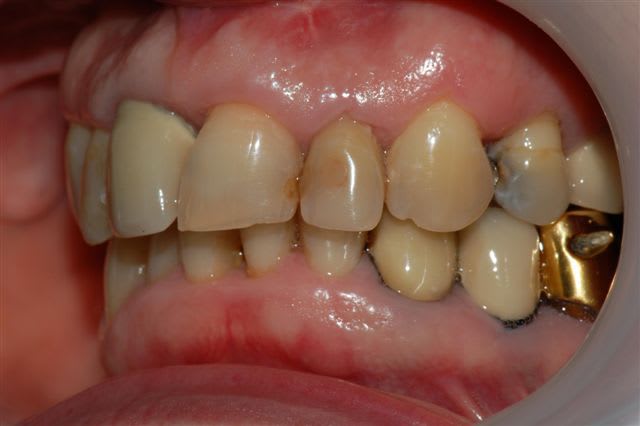

voici un cas traité en dentisterie globale à l'aide du laser en paro et du cerec en occluso, le cas à été terminé en 2010, cette semaine examen microbiologique de routine avec maintenance paro, il n'y a plus de flore pathologique dans la bouche de cette patiente

emma écrivait:

> voici un cas traité en dentisterie globale à l'aide du laser en paro et du cerec

> en occluso, le cas à été terminé en 2010, cette semaine examen microbiologique

> de routine avec maintenance paro, il n'y a plus de flore pathologique dans la

> bouche de cette patiente

>

> Emma

Reste plus qu'à faire des greffes de gencives secteur 4.

salut ceramik, toujours aussi contente de te lire, tes désirs sont des ordres, radios faites en 2010, les photos dates de juin 2010, les papilles entre 11 et 21 sont entrain de se reconstruire petit à petit, au prochain contrôle de maintenance, je ferai des radios et des photos pour montrer l'évolution engendrée par la biostimulation laser diode.

Joli cas Emma, juste une remarque, le travail de l'espace inter incisif en jouant sur la convexité des profils d'émergence masquerait le manque immédiat de papille et à terme la papille se reconstruirait plus rapidement.

Il est vrai qu'au vu de la difficulté initiale du cas ce type de détail peut passer à la trappe.

très belle reconstruction par cfao directe!!!!!

merci vm, en effet, le cas était plutôt complexe, comme la plupart des cas en dentisterie globale, mais ce que je voulais souligner, c'est que le Cerec pour ne pas le nommer permet de rendre de grands services.